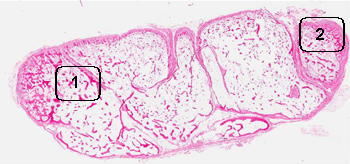

Hematoxylin & eosin

Area 1: Note that the bone at the internal part of the nodule is composed of mature, lamellar bone.

Area 2: These images illustrate the ossifying process of the shell of the lesion.

Histologic Highlights of this Case:

• The nodule is composed of a calcified shell of bone and scant islands of cartilage (not shown in this image). The internal part of the nodule is composed exclusively of mature adipose tissue and calcifying bone. No fibrous proliferation of inflammatory cells are present. No mature bone marrow elements are found.